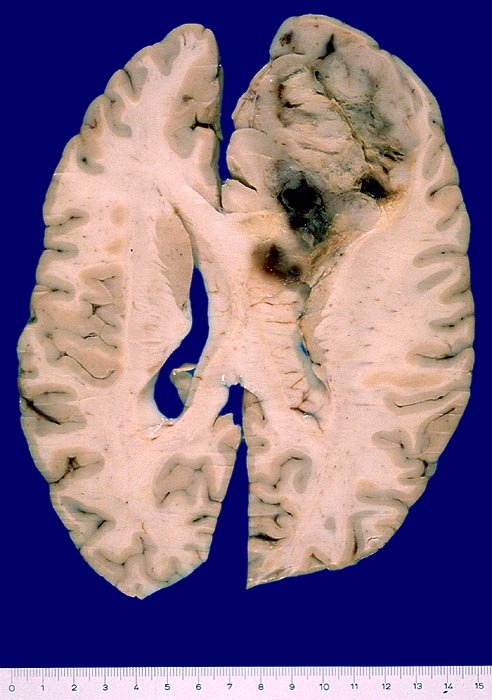

Die meisten Tumoren sind solitär und kortikal oder subkortikal in einer Grosshirnhemisphäre lokalisiert, am häufigsten frontal. Gelegentlich können sie primär intraventrikulär auftreten.

Makroskopisch sind die Tumoren gut begrenzt, solide und graurosa. Fokale Verkalkungen sind häufig, Nekrosen und zystische Degeneration können vorkommen. Intratumorale Einblutungen sind oft vorhanden und können die Todesursache darstellen.